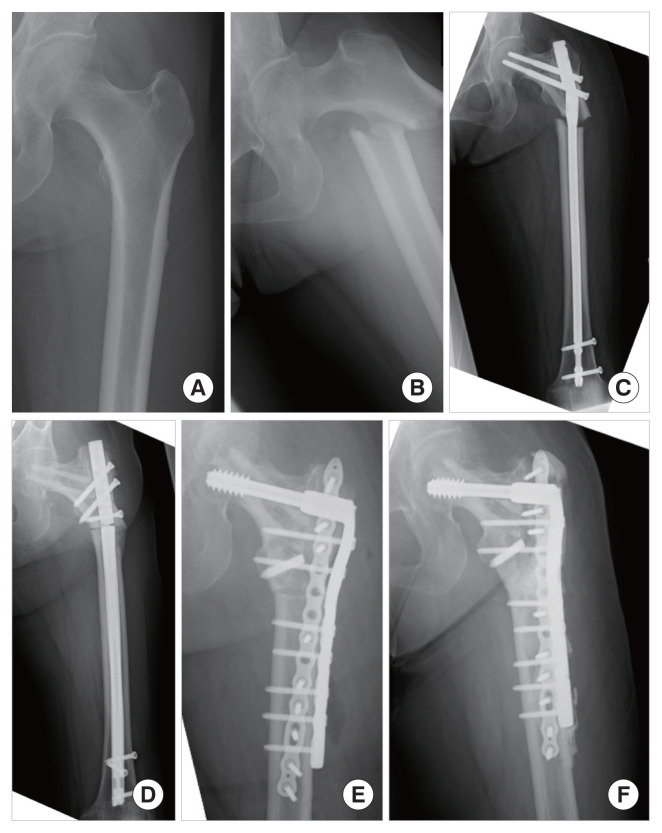

背景:前驱症状可能导致非典型股骨骨折(AFF)的早期诊断。然而,不完全AFF可发展为完全性骨折,因为它们经常被误诊为退行性疾病,如腰椎管狭窄或膝、髋骨关节炎。本研究的目的是在一项多中心研究中检查有多少aff被误诊为退行性疾病以及前驱症状部位的特征。方法:回顾性分析两所医院af患者的病历。此外,还向附属机构发送了一份调查问卷,以收集有关前驱症状的数据。结果:两所医院的分析显示35例患者46例aff。17例骨折伴有腹股沟或大腿外侧的局限性前驱症状(常规型),12例骨折有不局限于骨折部位的前驱症状,如广泛的大腿外侧、膝关节或小腿外侧(改良型)。11例骨折误诊为退行性疾病。对11个附属机构的调查显示,49例af患者中有29例报告前驱疼痛。其中19例骨折伴有改良的前驱疼痛,9例骨折被误诊为退行性疾病。结论:21%的af被误诊为退行性疾病。所有误诊病例均伴有前驱症状。我们认为AFF的前驱症状多样,与退行性疾病非常相似,这可能是导致误诊的原因。

Background: Prodromal symptoms might lead to an early diagnosis of atypical femoral fracture (AFF). However, incomplete AFF can progress to complete fractures because they are often misdiagnosed as degenerative diseases such as lumbar canal stenosis or knee and hip osteoarthritis. The purpose of this study was to examine how many AFFs are misdiagnosed as degenerative diseases and the characteristics of the site of prodromal symptoms in a multicenter study.

Methods: We retrospectively analyzed the medical records of patients with AFFs at two institutions. In addition, a survey was sent to affiliated institutions to collect data on prodromal symptoms.

Results: Analysis in two institutions revealed 46 AFFs in 35 patients. Seventeen fractures were associated with localized prodromal symptoms in the groin or lateral thigh (conventional type), and 12 fractures had prodromal symptoms not localized to the fracture site, such as widespread lateral thigh, knee, or lateral lower leg (modified type). Eleven fractures were misdiagnosed as degenerative diseases. The survey of 11 affiliated institutions revealed that prodromal pain was reported in 29 of 49 AFFs. Nineteen fractures were associated with modified prodromal pain, and 9 fractures were misdiagnosed as degenerative diseases.

Conclusions: Twenty-one percent of AFFs were misdiagnosed with degenerative diseases. All of the misdiagnosed cases were associated with prodromal symptoms. We believe that the prodromal symptoms of AFF are diverse and very similar to those of degenerative diseases, which may have caused the misdiagnosis.